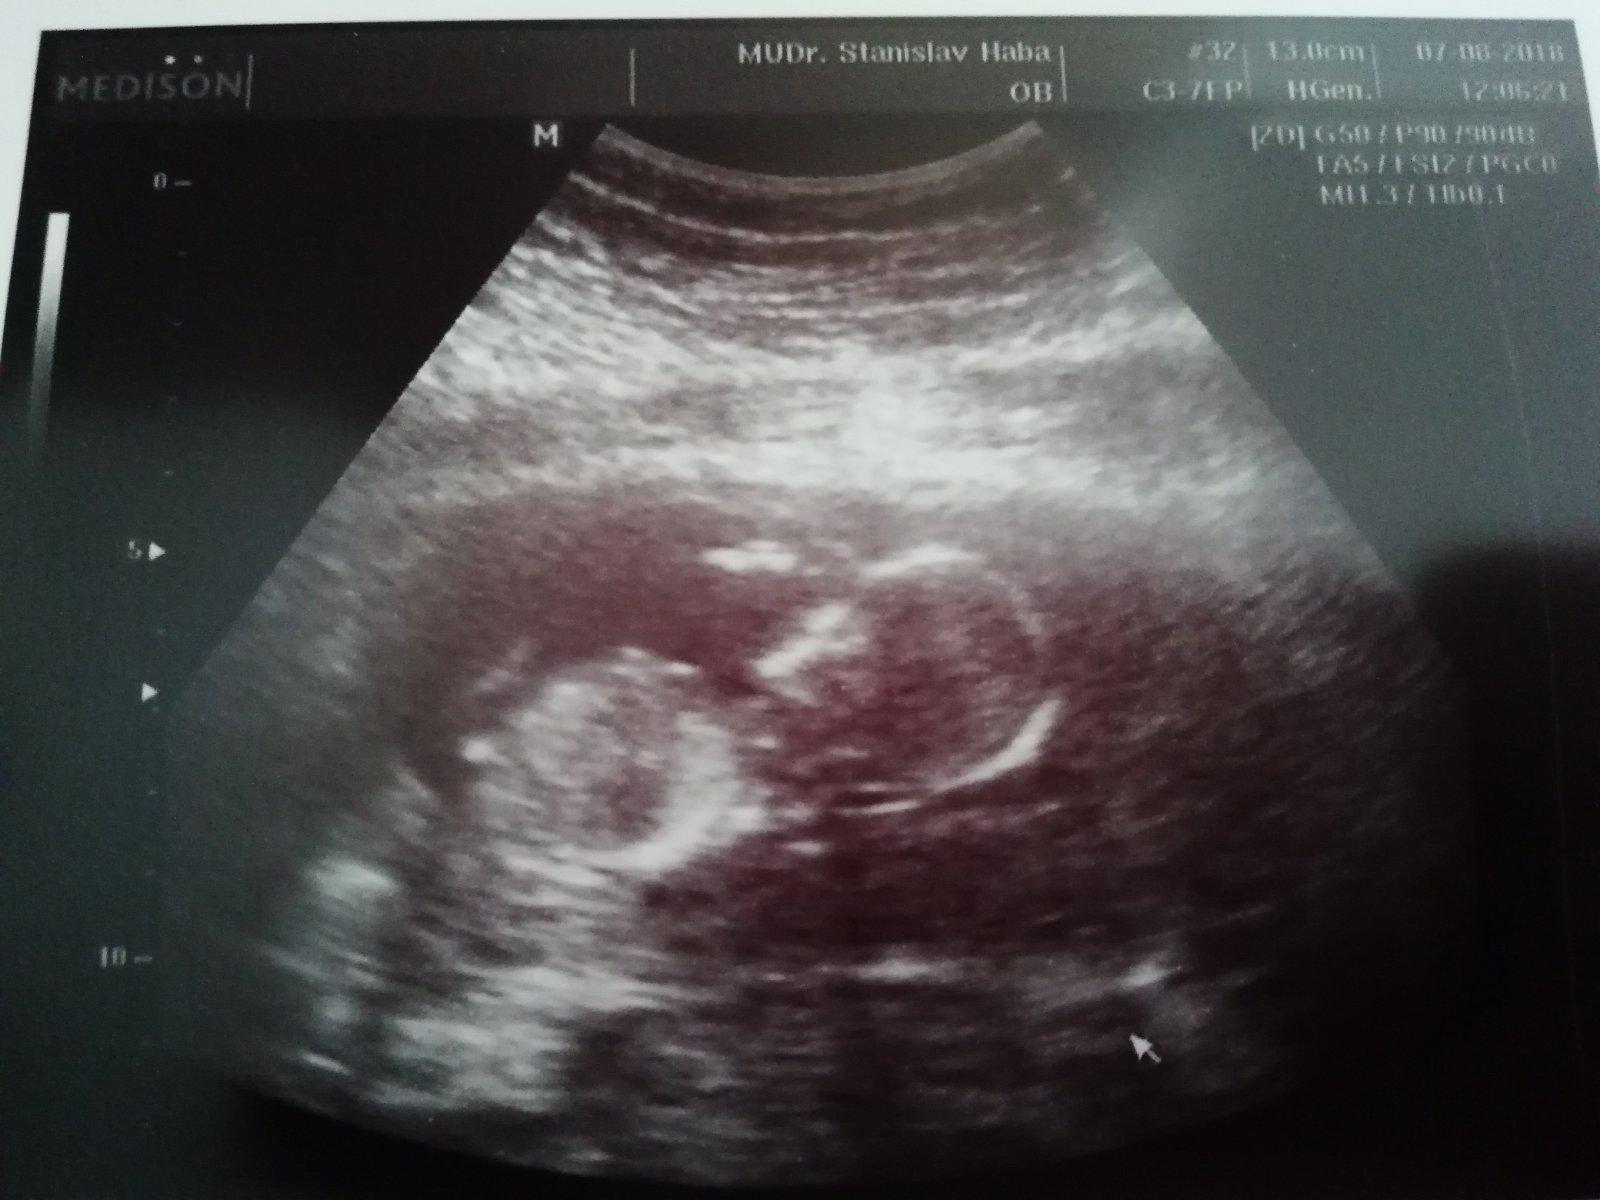

Tak se hlásím po kontrole, prcek pěkně řádil, ruka za hlavou, kopáníčko. Dostala jsem výsledky screeningu, termín mi sedí na den, takže zůstává 1.2. a dnes jsem 14+4, další kontrola 17+3, to už se pokusím i vymámit z dr. pohlaví.

A gratuluji, už jsou ty dětičky zase o něco větší, já dnes byla unešená z těch mini prstíků 😃 Vypadá to jako chlapeček 😃 myslím ta tvoje fotka z utz :D ale to klidně může být pepeční šnura.

@frndafrrr Já to pak upravila, jelikož to vyznělo jako že mi řekli pohlaví :D to neřekli,ale rotažený bylo krásně :D

@dominika963852 To bude spíš pupečník, nebo nožička. Já taky všechny obrázky studuju, jestli tam něco uvidím.